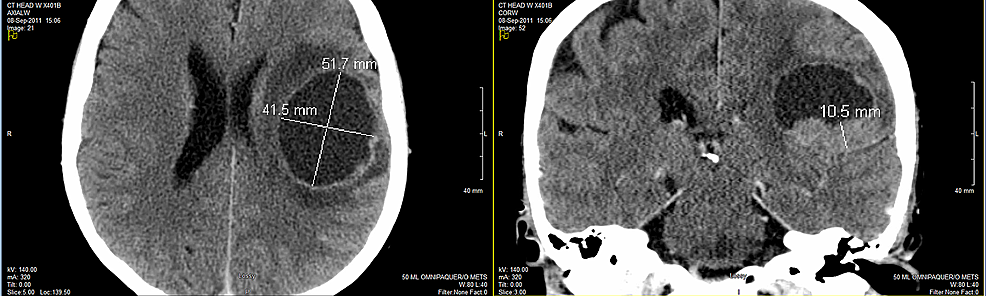

Brain metastases are a common complication in a wide range of cancers, but they are particularly common among patients with lung cancer. It is characterized by rapid, uncontrolled growth of certain cells in the lungs. Small cell lung cancer (sclc) is an aggressive form of lung cancer. Metastasis is the main cause of death in cancer patients but remains a poorly understood process.